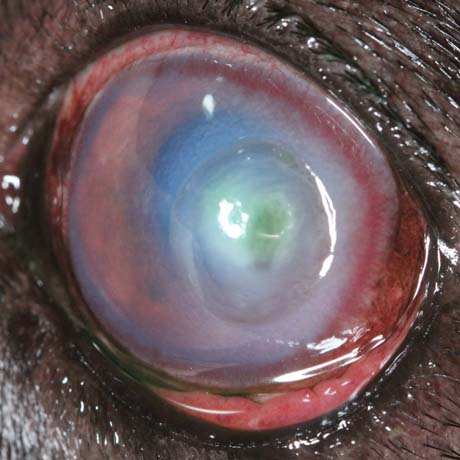

Nas patologias oftálmicas, o intervalo de tempo decorrido entre o inicio dos sintomas e a implementação do tratamento médico ou cirurgico, é fundamental para um desfecho de sucesso.